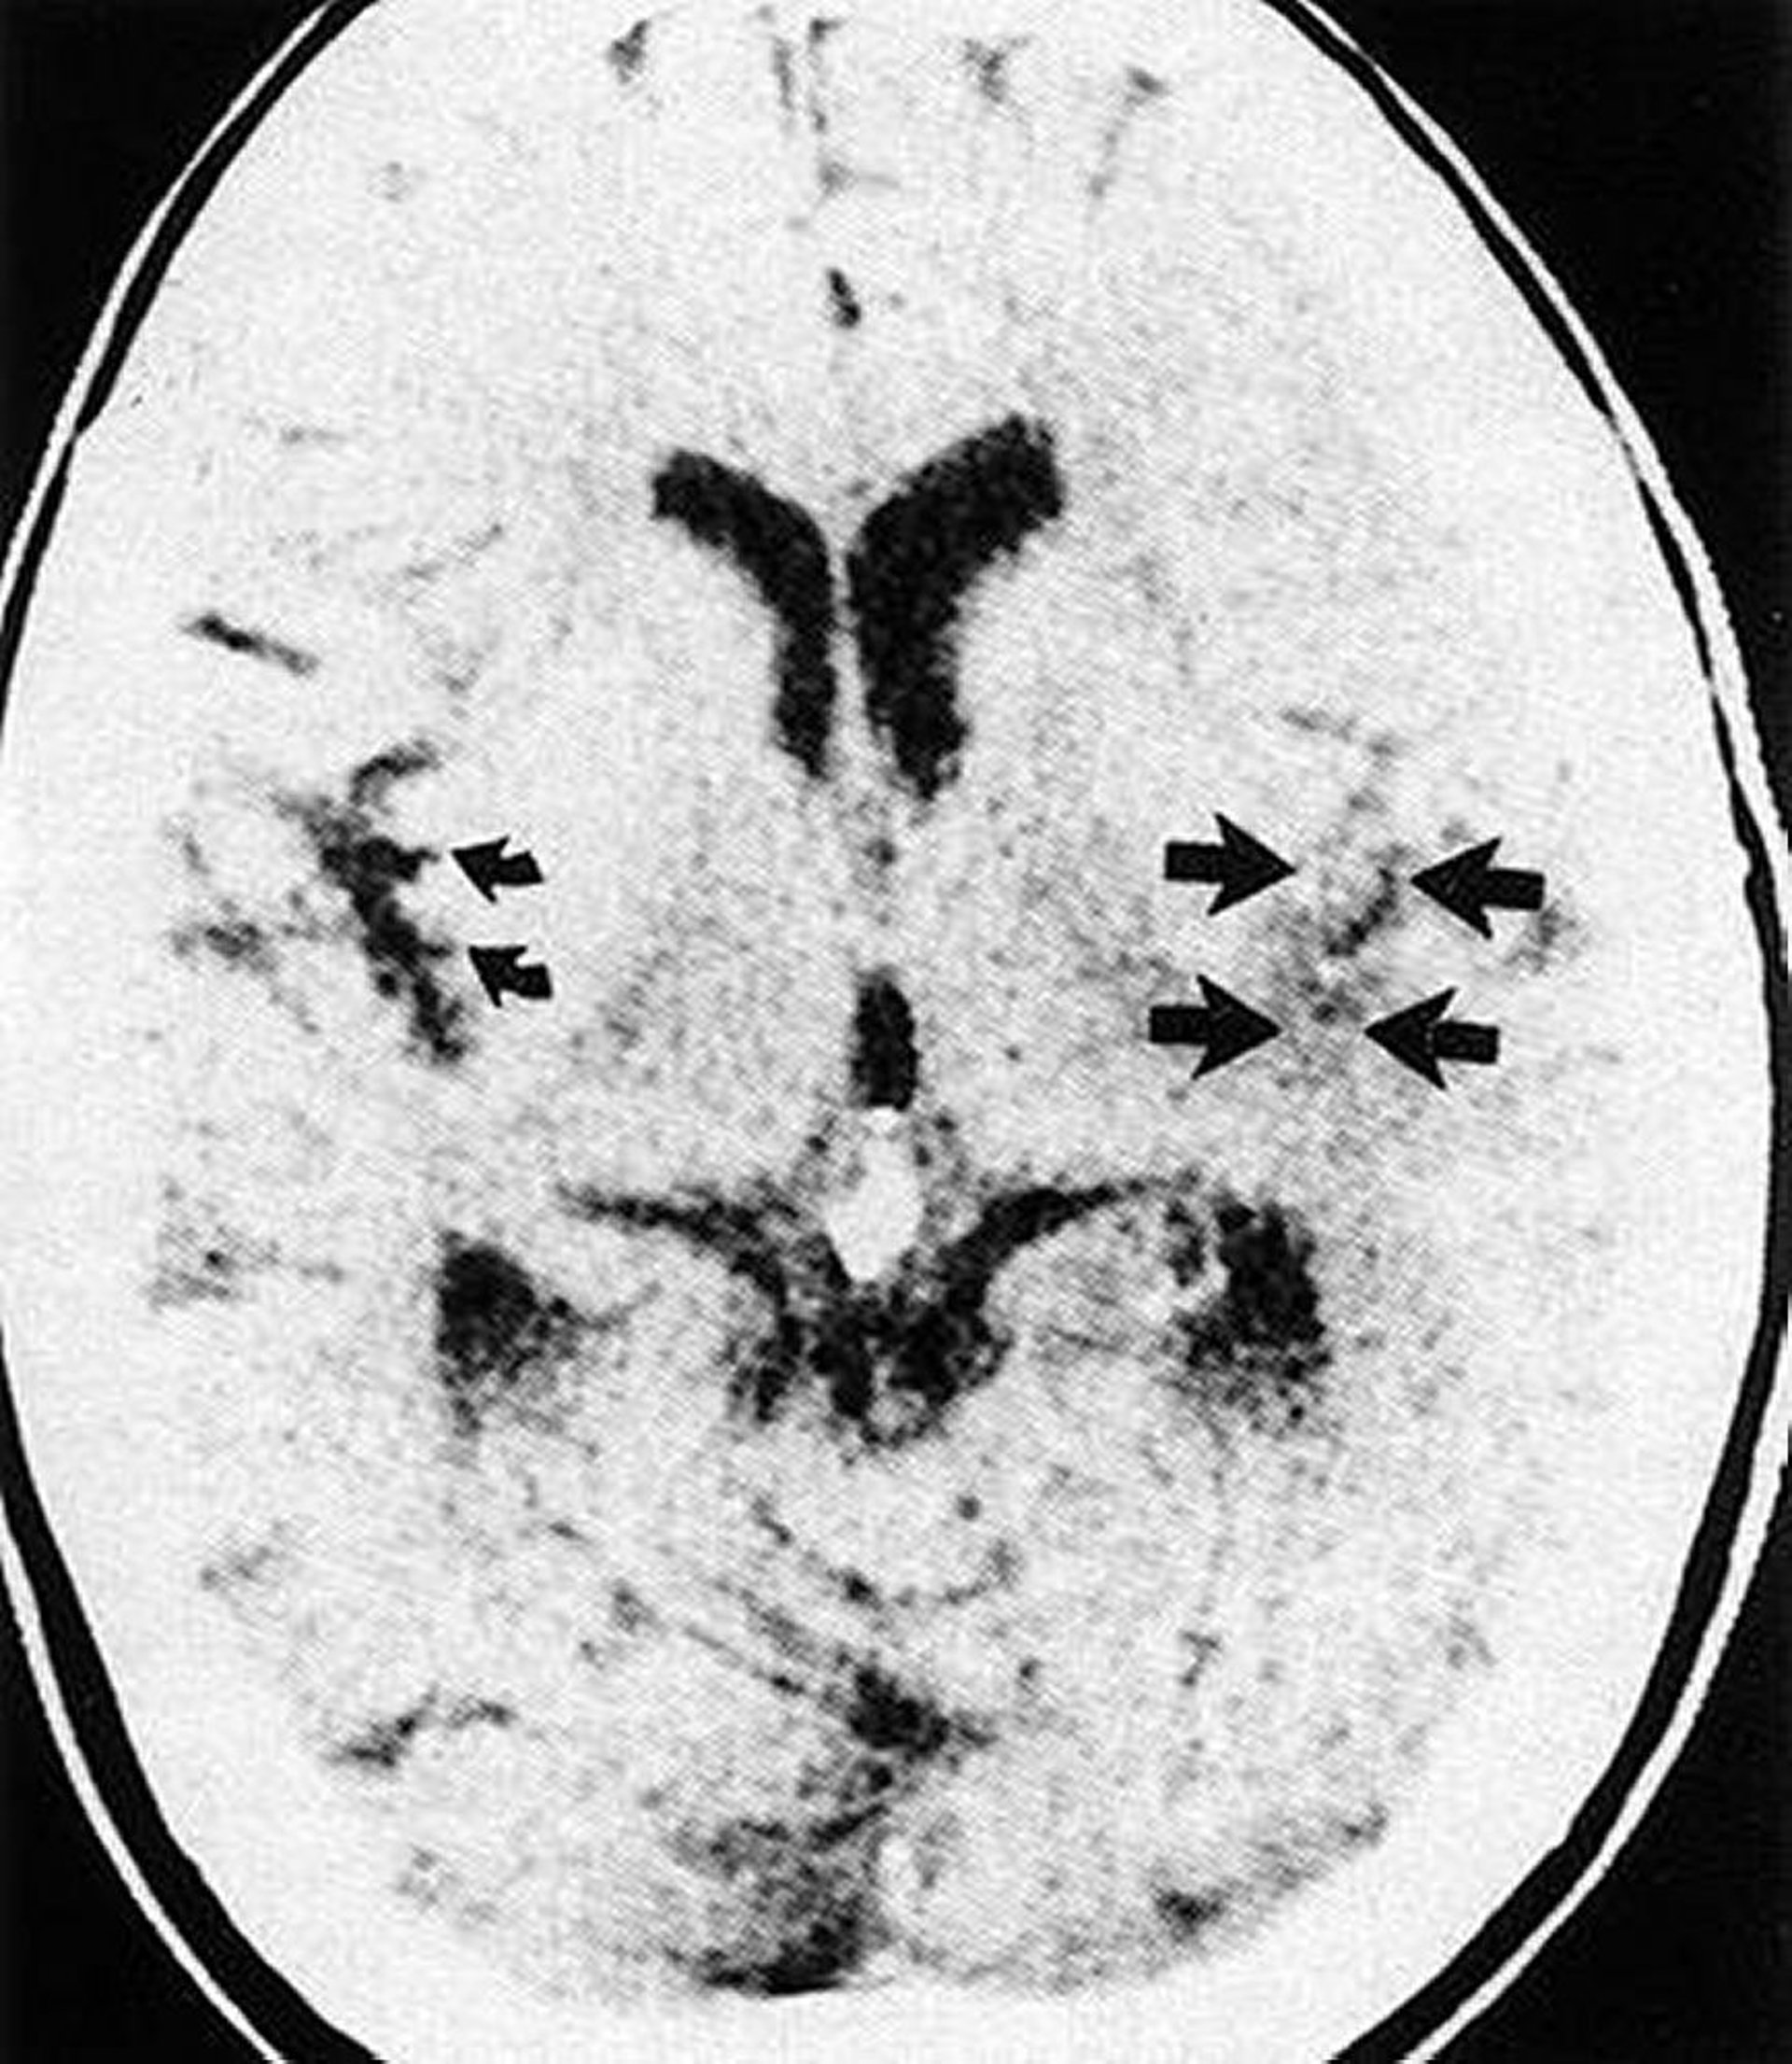

Perte de ruban insulaire

Cette TDM montre l'effacement de la scissure et du ruban insulaire sylvien (flèches droites) du côté infarci du cerveau par rapport au ruban insulaire normal (flèches courbes).

By permission of the publisher. From Geremia G, Greenlee W. In Atlas of Cerebrovascular Disease. Edited by PB Gorelick and MA Sloan. Philadelphia, Current Medicine, 1996.